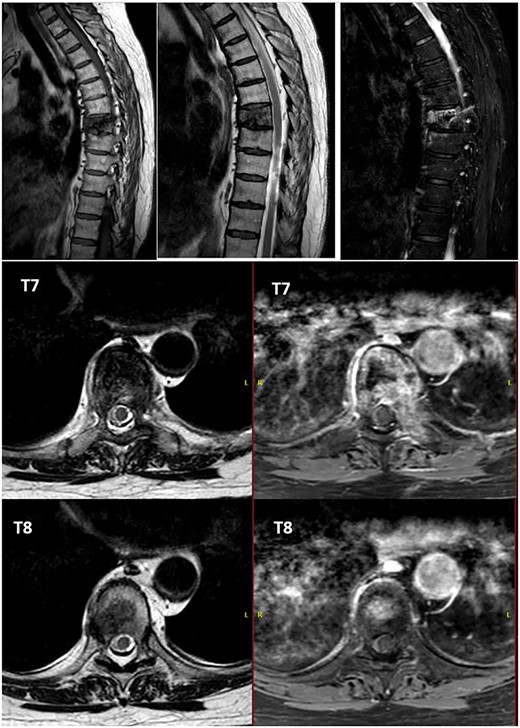

Alteration in the morphology and signal of the T7 vertebral body that presents a fracture with 30% loss of height and dorsal protrusion of posterior wall, with a left and epidural soft tissue component, the signal change extends to the left pedicle and part of the posterior arch. The right lateral margin of T8 vertebral body presents a hypointense signal on T1 and markedly hyperintense on STIR that indicates the presence of osseous edema. These findings suggest T7 pathological fracture and bone edema in the left T8 pedicle.

After PET scan, metastatic disease was discarded. Complete spine magnetic resonance and thoraco-abdominopelvic CT indicated the location on T7 vertebral body, with both end plates broken and causing a leakage to intervertebral disks. Moreover, an intensity change in the left pedicle of T8 was found, which could not be discarded as tumoral (Figs 2 and 3). Surgical resection been the only possible treatment, the patient was appointed to undergo total en bloc vertebrectomy of T7 and T8 and partial of caudal T6, following the technique described by Tomita et al. [1]

T7 pathological fracture with breakage of both superior and inferior end plates. Cement from the performed kyphoplasty is present, with leakage into the anterior paravertebral space.